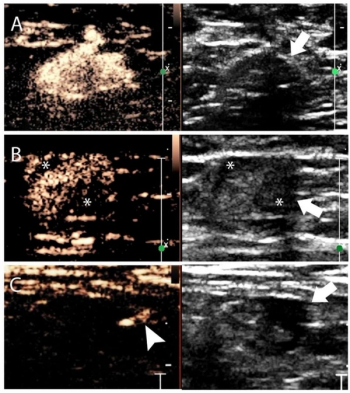

Emerging research suggests that combining full-field digital mammography and whole-breast ultrasound tomography provides superior sensitivity in detecting BI-RADS 4 lesions and superior specificity in diagnosing BI-RADS 3 lesions than mammography alone in women with dense breasts.